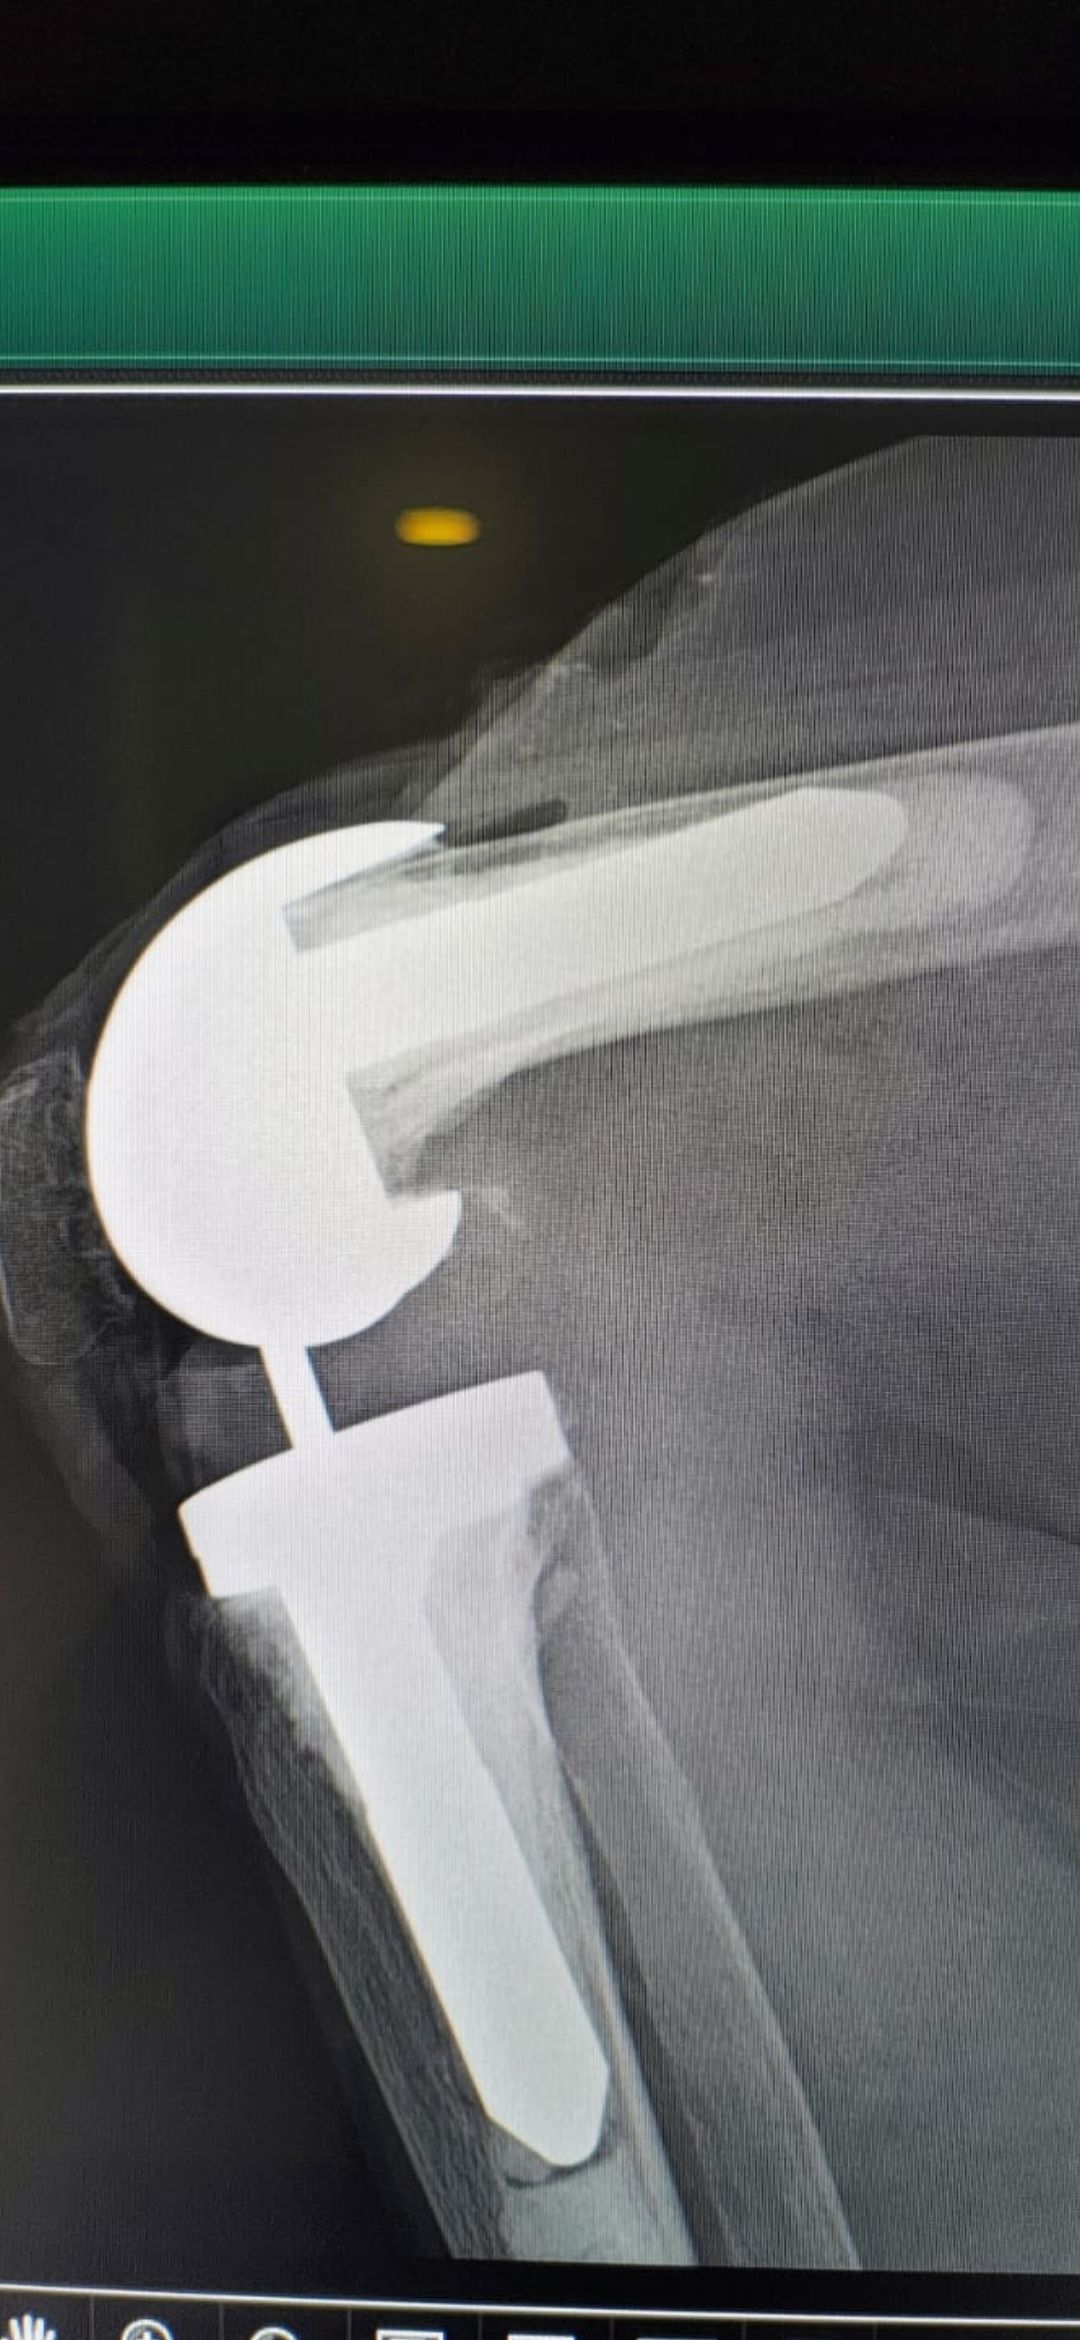

Soy   egresado  de  la  Universidad Autonoma de   Nuevo  Leon. especialidad de ortopedia y traumatologia  en    hospital  numero  21  del  IMSS ne Monterrey  N.L ,con entrenamiento en la  subespecialidad  de   reconstrucion  articular  y  artroscopia  que incluye  lesiones  de  meniscos  , reconstruccion de ligamentos cruzados , lesiones  condrales ,  gonartrosis   tengo  una  historia laboral    institucional de 30  años    hasta el 30  de lulio del 2024 estuve  10  años  en  el  modulo  de  artroscopia  con aproximadamente   1120    artroscopias  de rodilla   y  15 años  en  el  departamento  de    artroplastia  de rodilla  o  de  reemplazos  articulares   ,  los  ultimos   15  años    como profesor  adjunto   y titular  en los cursos    de pre  y posgrados  de  traumatologos  en la  subespecialidad  de  con aproximadamente   160 cirugias  institucionales    en   artroplastia de  rodilla    por  cada año   y  un  numero menor en el  medio particular  dando un total  aproximado  de  2,560  cirugias . de  estas  el  10%    de  revision  y  5%  preotesis    tumorales    de  actualmente   en  funciones  en  el  medio privado  y  acreditado  en todos los  hospitales  de la  localidad  y  con todas  las  aseguradoras   de  gastos  medicos .